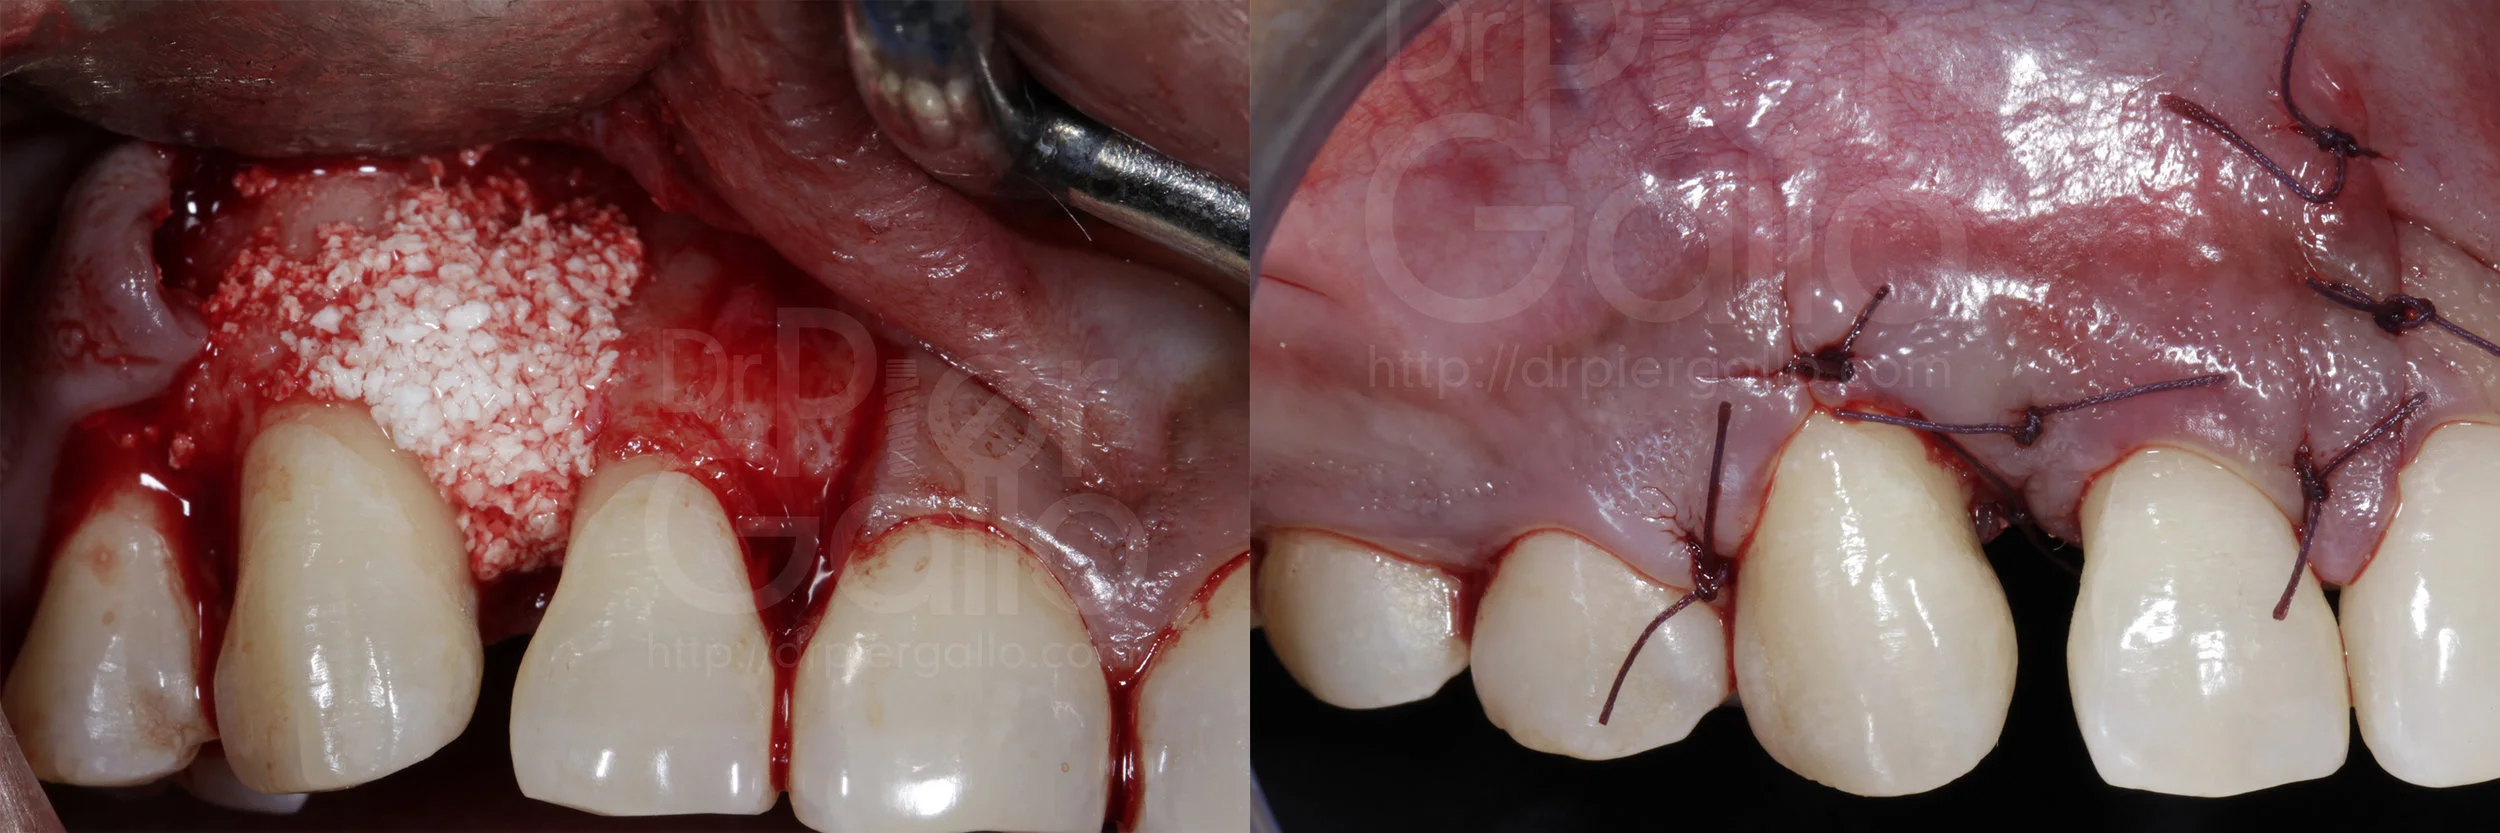

Posteriormente se levanta un colgajo de espesor total de 12 a distal del 13, con relajante en mesial del 12.

Luego de retirar el tejido granulomatoso, se procede a raspar y alisar la raíz del diente ·13 y a colocar el injerto rhPDGF-BB+ß-TCP. Por ultimo, se reposiciona el tejido blando y se sutura con Vicryl 4 ceros.